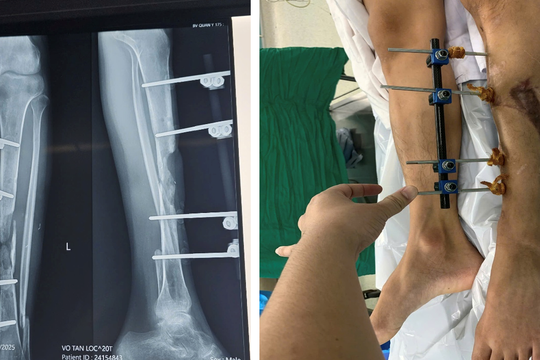

Kỳ tích tái tạo xương chày bằng vi phẫu cho bệnh nhân

Bệnh viện Quân y 175, TP.HCM vừa phẫu thuật thành công ca tái tạo xương chày phức tạp bằng kỹ thuật vi phẫu chuyển vạt da-cân-cơ xương mác tự do, đánh dấu bước tiến mới trong lĩnh vực tạo hình vi phẫu tại Viện Chấn thương Chỉnh hình.